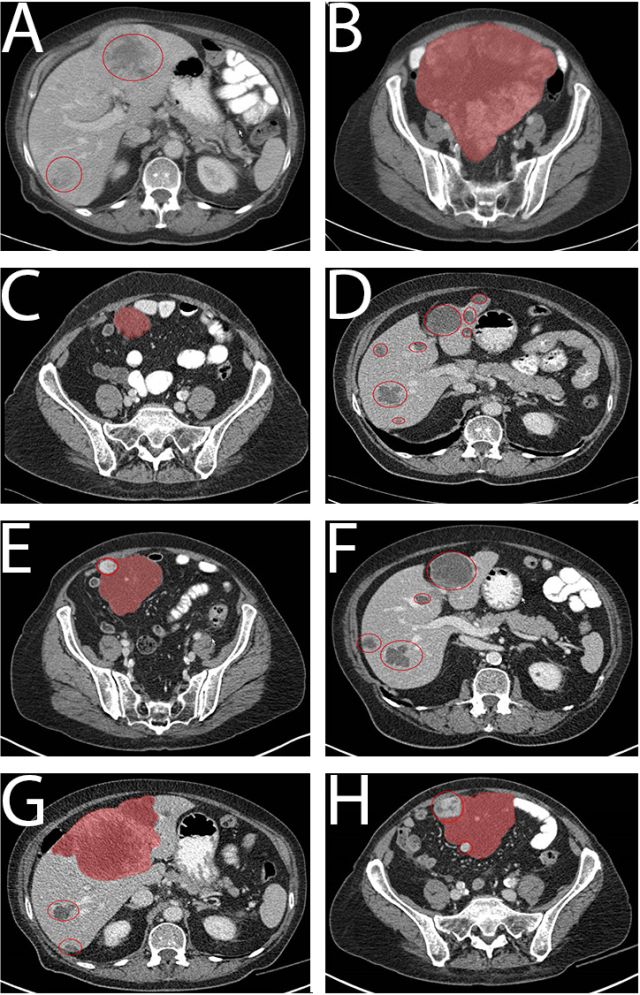

病例1为一个76岁的老年男性,腹部巨大包块(29cm,图1A)),ECOG 3,穿刺证实为GIST,PDGFRα外显子18突变 (NM_006206.5: c.2531_2542del; p.(M844-S847del))。一线给予伊马替尼400mg qd,一周后恶心症状就缓解了,并且生活质量明显改善。治疗持续了1年,最佳疗效为SD(每3月CT评估)。随之腹膜出现了新病灶(图1B),第15个月时调整为二线治疗药物索坦 37.5mg qd。病情在服药后1年内得到良好控制(图1C)。1年后出现PD,中等量腹水(图1D)。经过引流后症状控制,肝脏出现多发转移灶并行穿刺活检,调整为三线药物瑞戈非尼(160mg qd, 3/4方案),PFS为5个月(图1E),并于PD停药后1月死亡(图1F),重新口服伊马替尼无效。患者在三线瑞戈非尼和四线伊马替尼治疗期间留取了血样,发现在1E和1F期间突变拷贝数增加(180-850拷贝/ml,图3A),最后一次随访(死亡前2周)时拷贝数达到4767拷贝/ml。

病例2为76岁的老年女性,因腹痛就诊,CT发现腹腔25cm的肿块伴多发肝转移(图2A和2B),肝穿刺活检提示CD117阳性GIST,突变分析未发现KIT突变,PDGFRα当时未检测。 一线给予伊马替尼400mg qd,10天后临床症状缓解,耐受性良好,3个月后获得PR(图2C 和2D),30个月后原发肿瘤和肝转移灶都出现了PD(图2E和2F)。重新分析原来标本的PDGFRα发现外显子18突变 (NM_006206.5: c.2527_2538del; p.(I843_ D846del))。患者接受了增量的伊马替尼(400mg BID),耐受性良好,但未获得疗效 (3个月后的CT评估,如图2G和2H)。随后调整为索坦37.5mg qd,但2个月后症状持续恶化,OS总共36个月。 由于组织标本采集困难,本例患者进行了血样的ctDNA分析(图3B) ,结果显示患者在伊马替尼治疗的第16.5个月时突变拷贝为6拷贝/ml,这个低水平一直维持到第30个月。在伊马替尼增量开始时为275拷贝/ml,第33个月增长为852拷贝/ml,索坦治疗启动后,一度降至208拷贝/ml,但因患者在第36个月死亡未再收集血样。

图2. 病例2的CT图像

图3. 治疗期间系列血样突变拷贝数分析